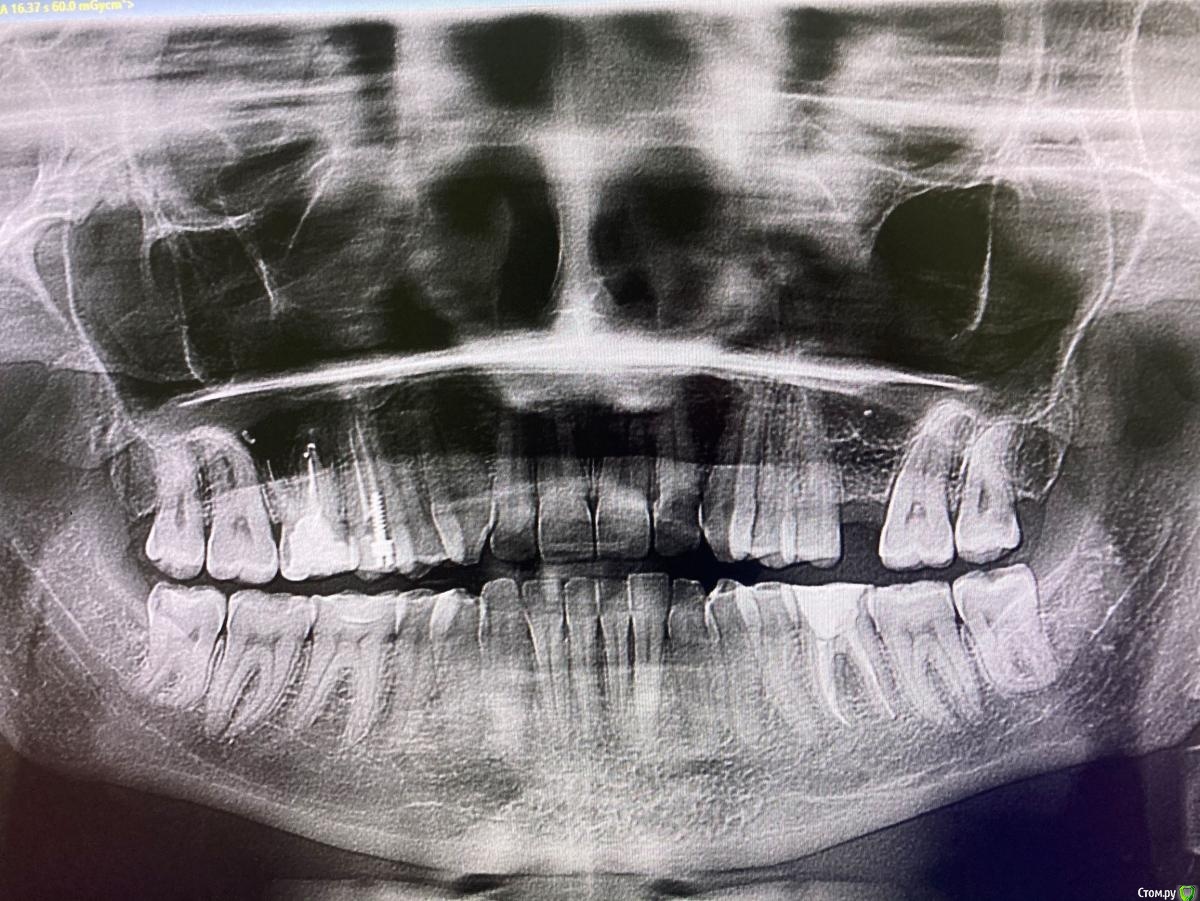

Эллина У. Опубликовано 8 февраля, 2021 Поделиться Опубликовано 8 февраля, 2021 Добрый день! Прошу посоветовать комплексное решение ситуации. Снимок во вложении, КТ тоже есть (пока не выкладываю). В 2015 году удалила верхнюю 6-ку слева (сейчас хочу сделать имплант), нижний ряд сдвинулся вправо, несколько зубов с клиновидным дефектом. Восьмые зубы не удаляла пока, они кариозные и сложные, как говорят (боюсь, но собираюсь). В февраля 2019 лечила верхние 5 и 6 справа. В конце января 2021 сделала КТ - оказалось, что при установке штифта на 6-ке была затронута гайморова пазуха, в нее попала пломбировочная жидкость (теперь понятно, почему в последнее время почти постоянная легкая заложенность слева, гайморит). По ощущениям - бывает, простреливает, отдает в ухо, дискомфорт. И 6ой зуб нижний слева, судя по КТ сказали, что там после лечения каналов что-то с костью (нет костной ткани между конями зуба ?). Тоже не постоянно, но есть дискомфорт, бывает тупая боль. Нижняя 6-ка справа тоже иногда побаливает (хотя ее состояние никак не комментировали - от перегруза?) В целом ощущения на этих трех оставшихся 6-ках не нравятся, беспокоят. Прошу дать рекомендации по порядку лечения: имплантации, передвижение зубов, что делать со всеми 6-ками!? Описала ситуацию, как я ее поняла после нескольких консультаций. На снимке, полагаю, не все это видно. Прим.: планирую беременность, поэтому хотелось бы управиться месяцев за 3-6 с теми процедурами, которые с беременностью несовместимы. Это реально?.. Заранее благодарю! Ссылка на комментарий

Bier Опубликовано 8 февраля, 2021 Поделиться Опубликовано 8 февраля, 2021 Здравствуйте! Костные условия неплохие. Потребуется закрытый синуслифтинг скорее всего. Но места под коронку 26 зуба (верхний 6 слева) нет. Потребуется отодвинуть 27й зуб назад, а 28 зуб удалить.Подвинуть зуб можно двумя способами: 1. Установить миниимплантат за 7м зубом и тянуть 7й к нему2. установить имплантат в 6ку, сделать на него узенькую временную коронку и от коронки толкнуть 7й зуб назад. Потом поменять на постоянную, нормального размера. Ссылка на комментарий